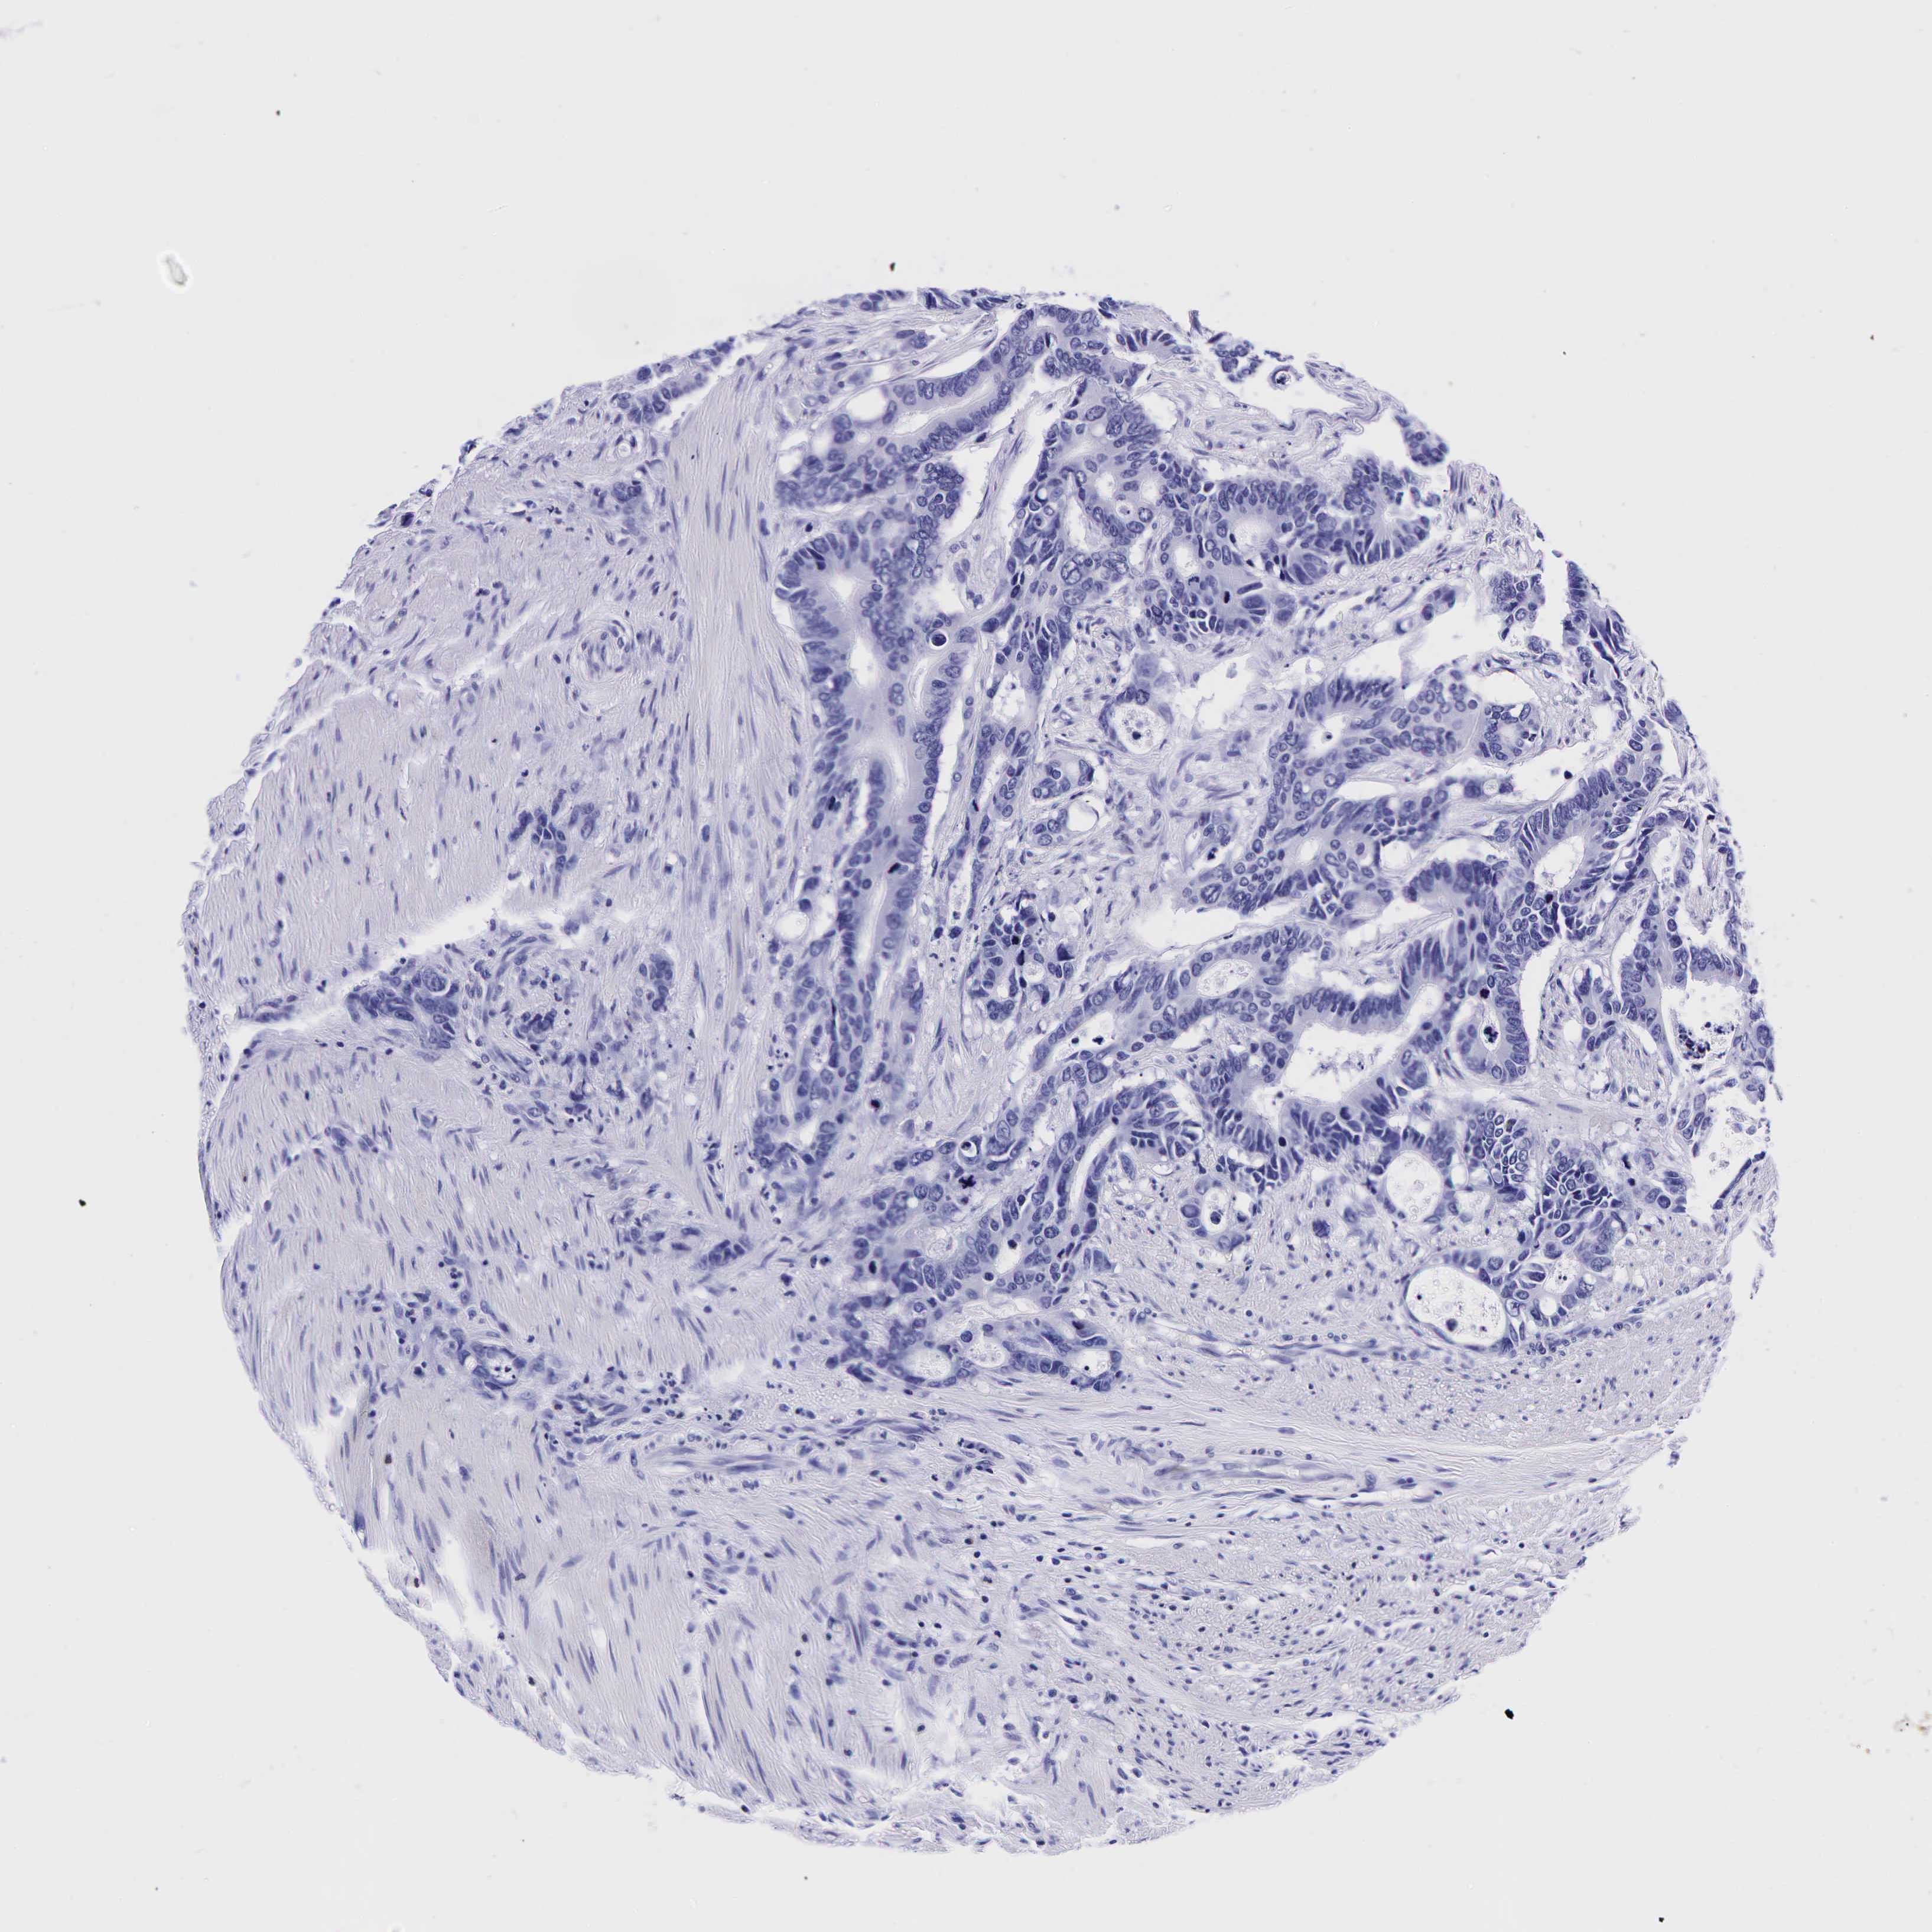

Colorectal cancer

Human cancer

Colon adenocarcinoma